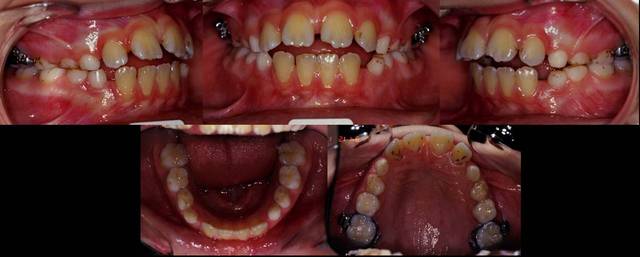

Pour repondre a la demande de bjc, voici un cas de bipro, sans extraction, sans brackets et sans fils a l'exception d'un QH et un ecran buccal. Un traitement purement musculaire avec recul des incisives haut et bas sans avoir besoin d'ancrage.

Notez les diastemes haut et bas, et la fermeture spontannee grace a la reeducation. Le profil fin de traitement, pas mal du tout n'est-ce pas bjc?

Les photos enfin, j'espere....

Le cas apres QH a ete sous surveillance pour voir si besoin d'autre chose, et vue l'occlusion comment elle se met en place, j'ai dit non. Je pourrais utilise un simple TP mais a l'epoque (cas traite en 1994) je ne sais pas pourquoi je ne l'ai pas fait, j'aurais du pour parfair les choses.